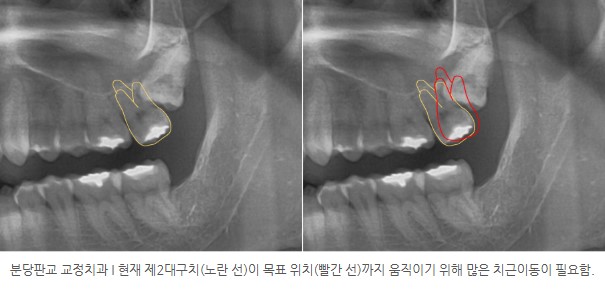

왜냐하면 기존 제2대구치를 이상적인 위치까지 이동시키려면

치아 몸체뿐 아니라 뿌리까지 많은 이동이 필요해 치료 효율과 안정성 측면에서 불리할 수 있기 때문입니다.